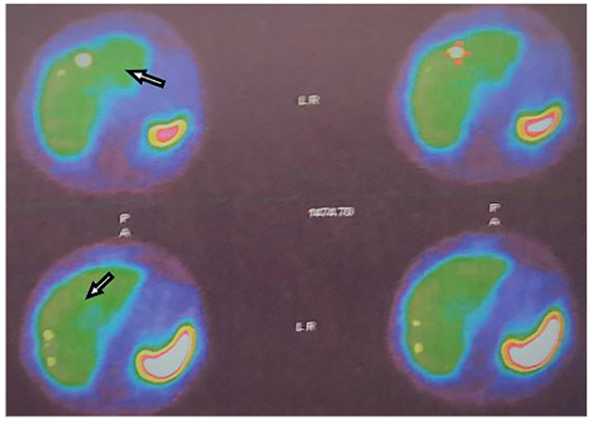

Se procedió a realizar un test de oclusión carotidea y una nueva cirugía, mediante abordaje por mandibulotomía y resección en bloque del tumor, con derivación carotidea intraoperatoria y reconstrucción con injerto de PTFE-e (figura 8), además de vaciamiento de cuello. El posoperatorio fue satisfactorio y la patología confirmó un carcinoma del glomus carotideo metastásico a 1 de 27 ganglios. Recibió radioterapia postquirúrgica IMRT 60 GY, en el seguimiento mediante un Octreoscan se encontraron metástasis hepáticas positivas (figura 9). Recibió somatostatina sistémica con excelente respuesta. Al año de seguimiento presentaba una enfermedad metastásica estable.